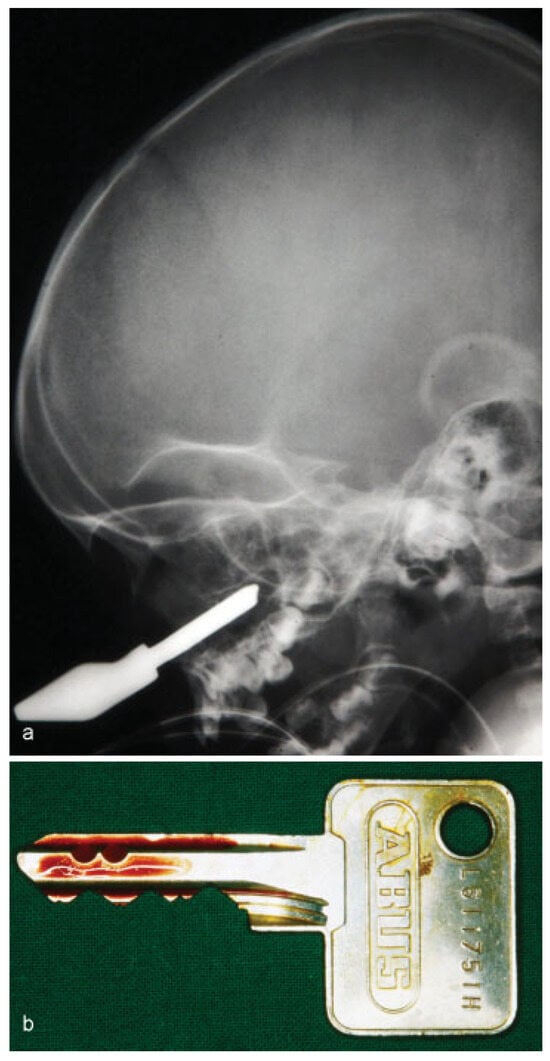

• Case 2: A 4-year-old girl was admitted to the emergency department after tripping while holding a key in her hands, ramming the foreign object into her cheek. Radiological examination confirmed perforation of the left maxillary sinus (Figure 2a). Surgical removal of the key was performed under general anesthesia (Figure 2b). The anterior wall of the maxillary sinus was flipped back without the need for osteosynthetic stabilization due to the young age of the patient. Wound healing showed no sequela.

Figure 2. (a) Lateral skull radiograph showing the radiopaque object penetrating the maxillary sinus. (b) Postoperative image of the removed key.